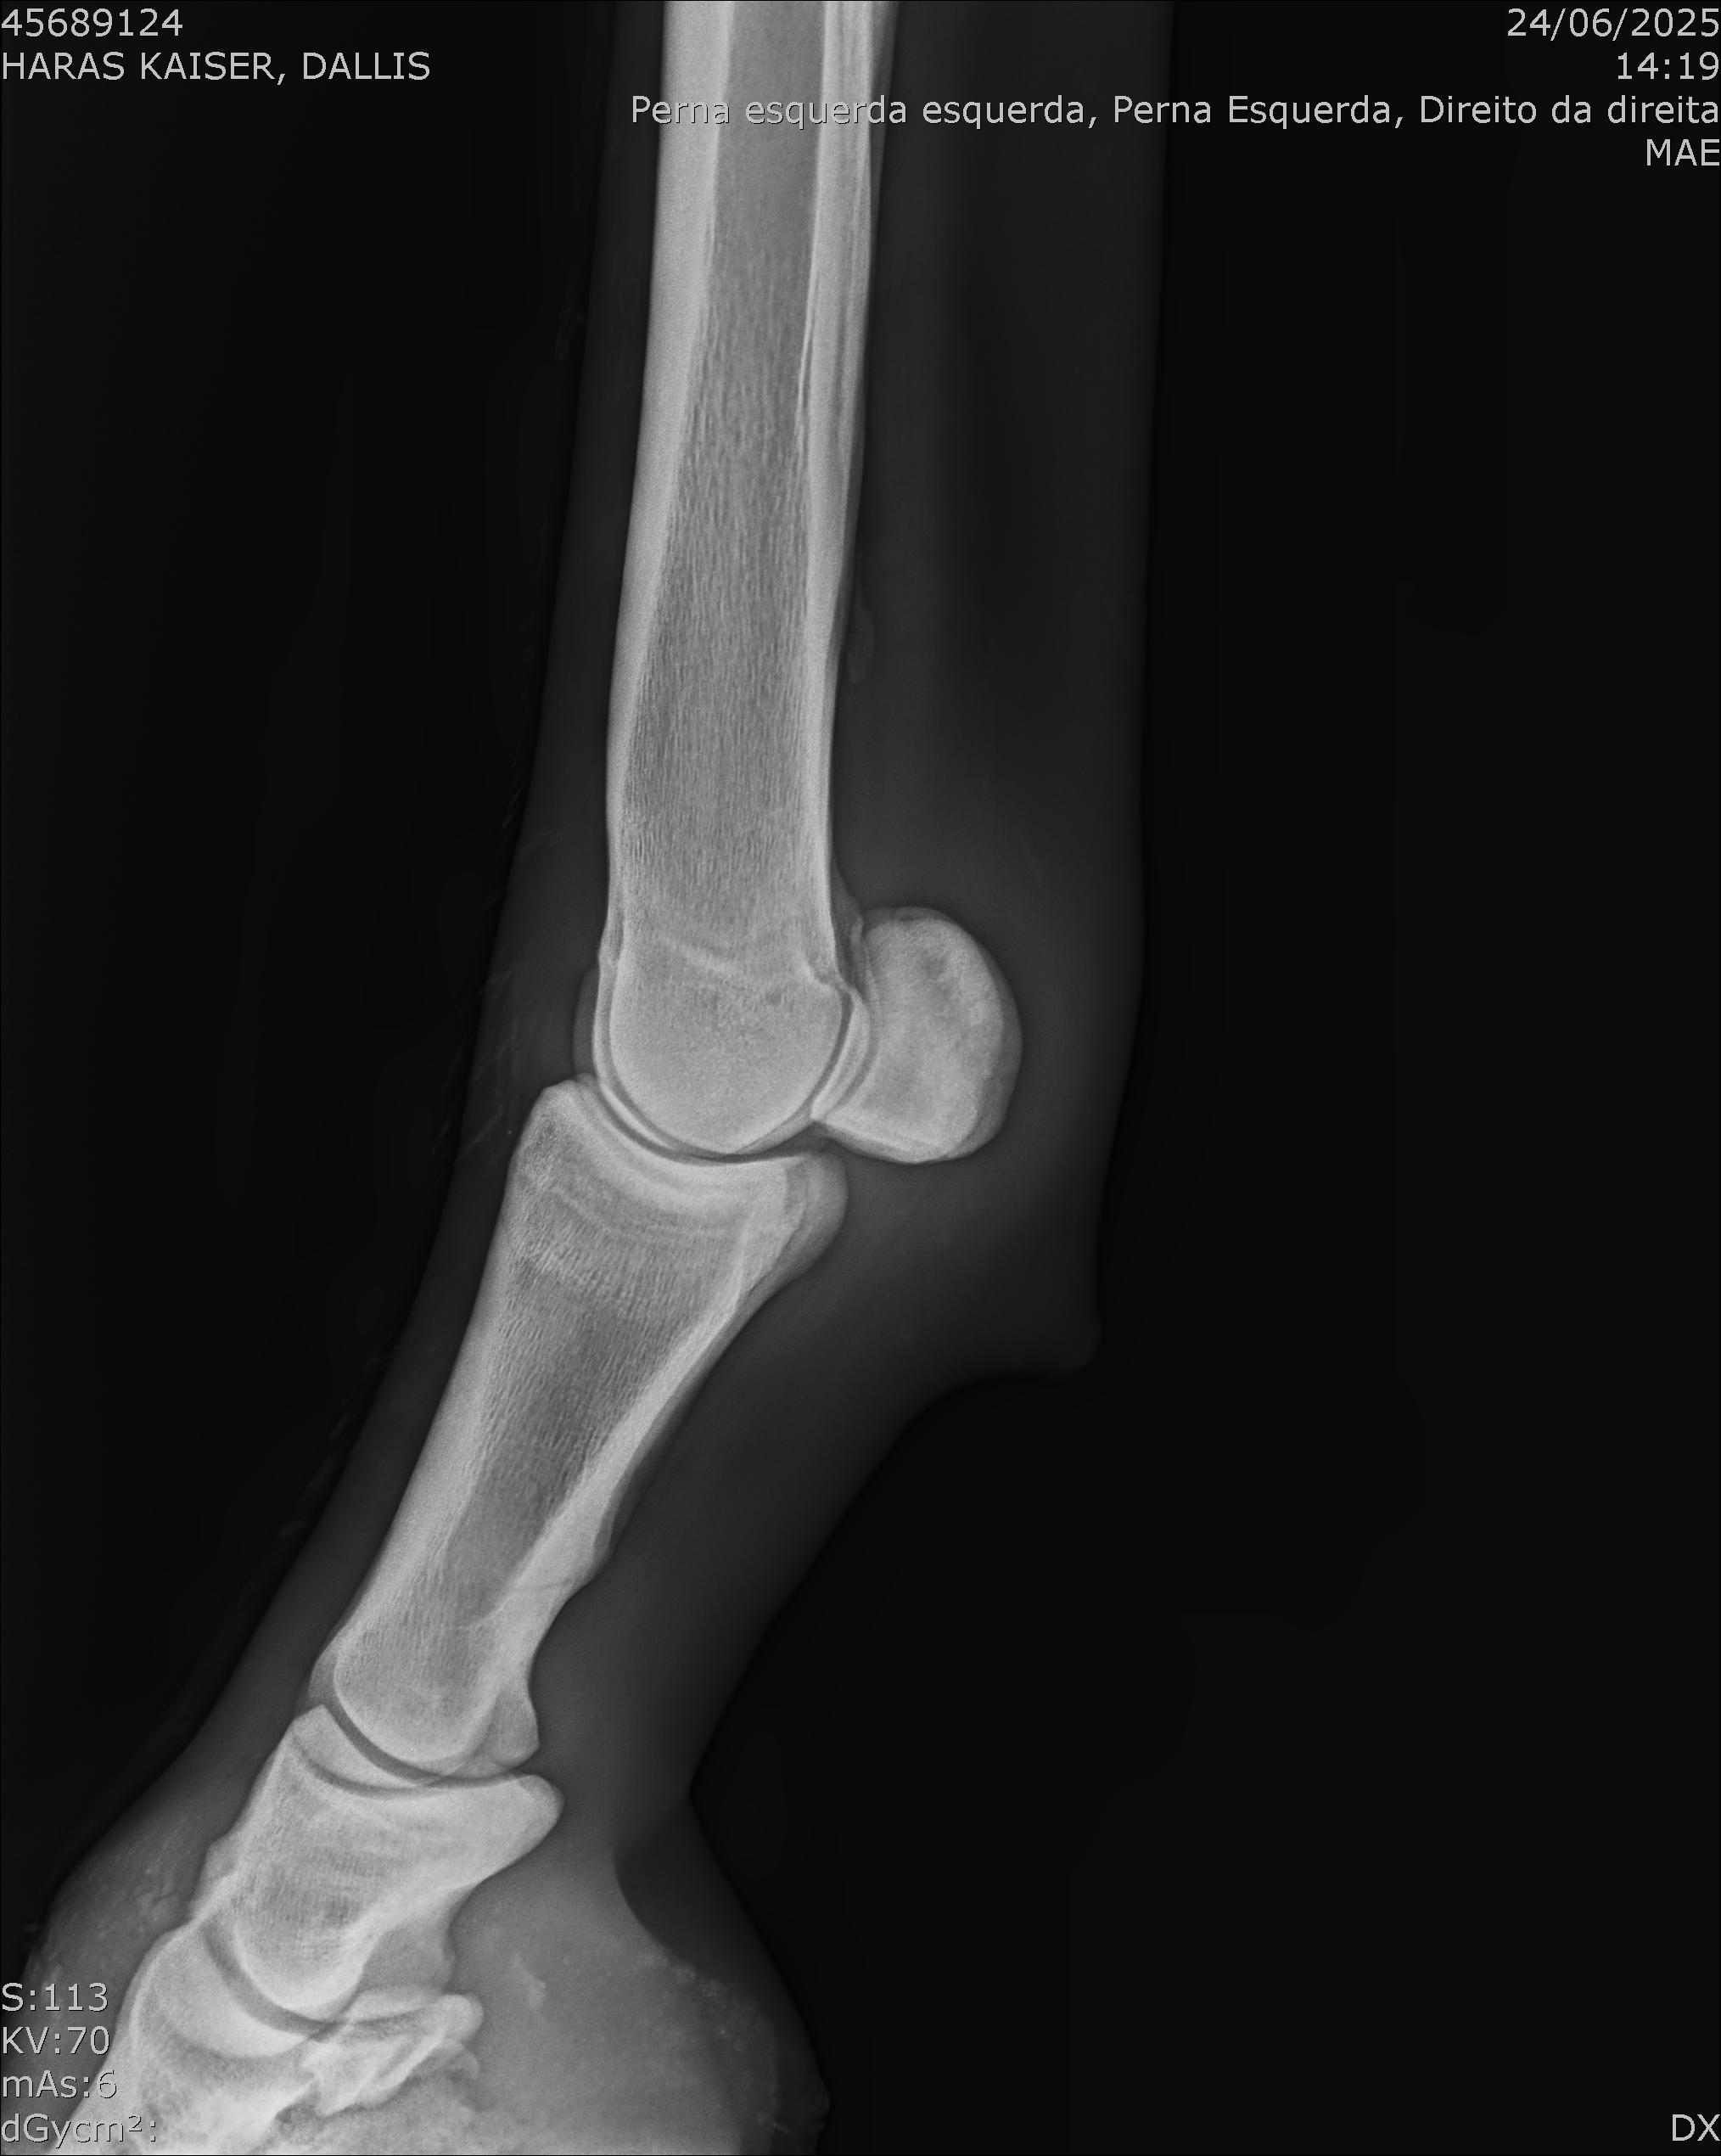

:: RAIOS-X DO LOTE